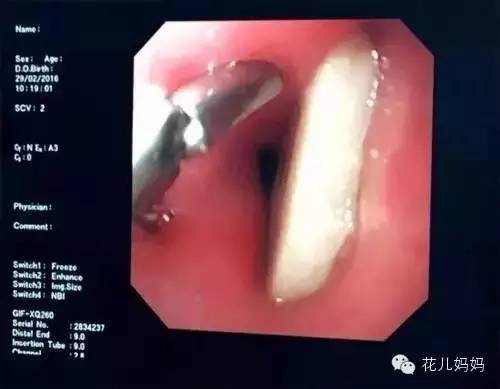

△照片里白色的块状物体就是牛骨头

主治医生李之印说,哲哲被卡的位置相当凶险,因为骨头刚好卡在了食管和主动脉交叉的位置,如果骨头穿透了主动脉,冒然取出一旦引发大出血,就会危及生命。

取骨头的手术在胃镜下实施,胸外科医生也在手术室里,万一手术中触到主动脉,就要进行开胸手术。医生试探性地轻摇了下骨头,发现还好,没有扎进主动脉,于是将骨头轻轻地取出,手术很顺利。医生说,做完手术后2天,哲哲还是不能吃东西,只能靠输营养液。